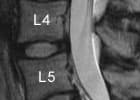

Es liegt eine krankhafte Verengung des Wirbelkanales vor (Stenose des Spinalkanales). Diese tritt in der Regel erst in höherem Alter auf. Sie wird verursacht durch:

• eine sich breitbasig vorwölbende Bandscheibe

• eine Verdickung des Bandapparates, welcher den Wirbelkanal auskleidet

• Verschleiß von Wirbeln und Wirbelgelenken, die knöcherne Anbauten entwickeln, welche in den Wirbelkanal hineinragen

Durch den zunehmenden Bandscheibendruck beim Gehen wölbt diese sich weiter in den Wirbelkanal vor. Die vorbeiziehenden Nerven werden „in die Zange genommen“, die Beschwerden treten auf.